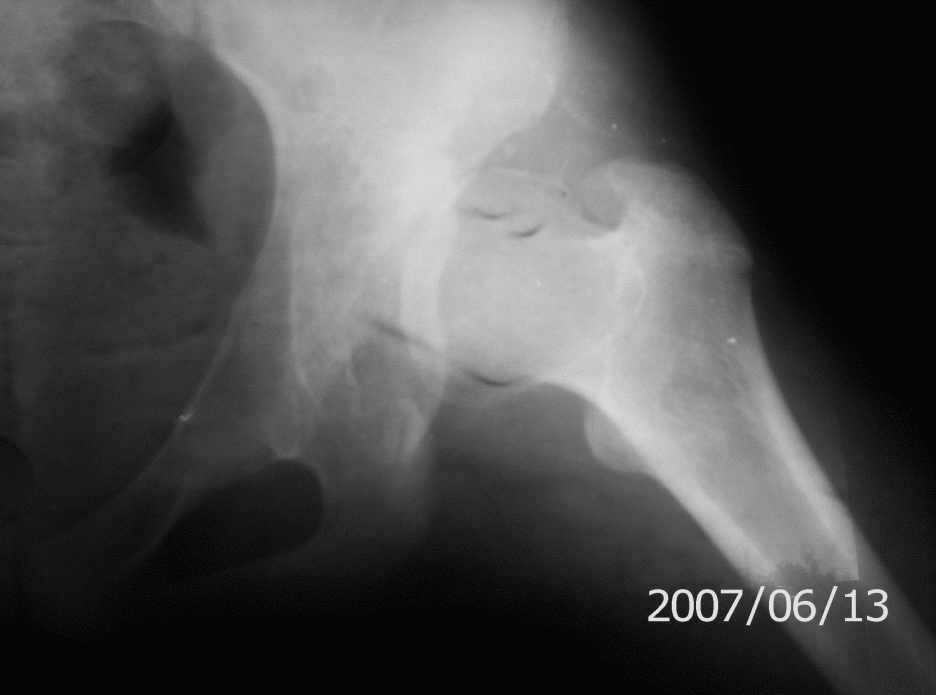

Prishlite poghaluista pelvis AP +frog

On x-rays coxa magna, shallow true + pseudoacetabulum.Options: salvage

Ацетабулюм крайне недоразвит. Есть высокий подвывих, можно даже сказать вывих с формированием ложного ацетабулюм. Для головки нет покрытия совсем и расположена она высоко.

На мой взгляд - SHORTENING OSTEOTOMY , VARUS если надо (на основании снимка во внутренней ротации), репозиция головки, CHIARI OSTEOTOMY или SHELF OPERATON Спасибо за интересный случай.